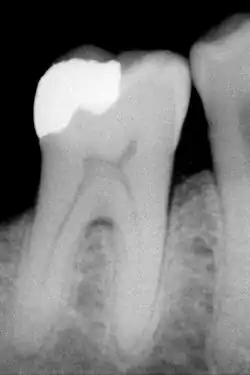

An X-ray showing enamel and dentin replaced by an amalgam restoration

Dental restorations

Most dental restorations involve the removal of enamel. Frequently, the purpose of removal is to gain access to the underlying decay in the dentin or inflammation in the pulp. This is typically the case in amalgam restorations and endodontic treatment.